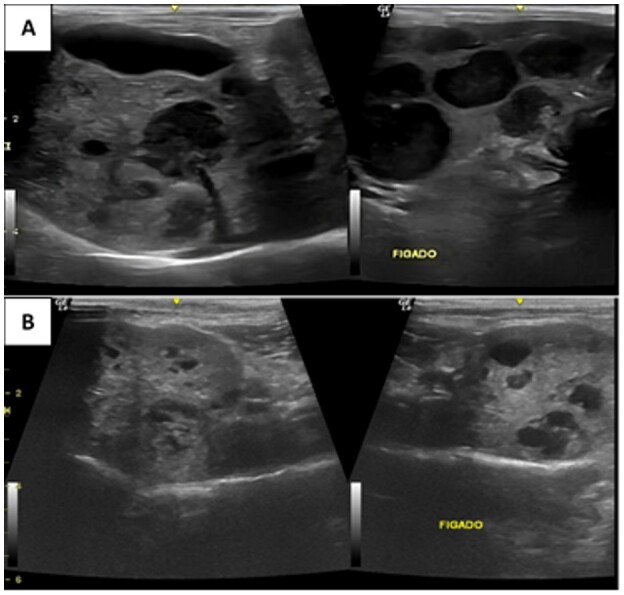

Gastrointestinal stromal tumors (GISTs) are uncommon mesenchymal tumors in cats that originate from interstitial cells of Cajal (ICC). ICCs are mesenchymal cells found within the muscle layers of the alimentary tract that facilitate communication between the autonomic nervous system and smooth muscles. In this case, lapatinib, a tyrosine kinase inhibitor (TKI) that targets EGFR1 and HER2, was used as part of precision therapy for metastatic GIST in an 8-year-old, 2.7 kg, spayed, female mixed-breed cat, guided by the high expression of these receptors in the tumor. The treatment resulted in partial remission of liver metastases, with a progression-free survival of 171 days and an overall survival of 192 days after starting lapatinib. Lapatinib was well tolerated, with minimal adverse gastrointestinal effects. These findings highlight the potential role of molecular profiling in guiding targeted therapy for feline GISTs and suggest that lapatinib may be a viable treatment option for EGFR1/HER2-positive tumors. Further studies are needed to evaluate the efficacy and safety of TKIs in veterinary oncology, as well as their impact on long-term survival and quality of life in feline patients with GISTs.